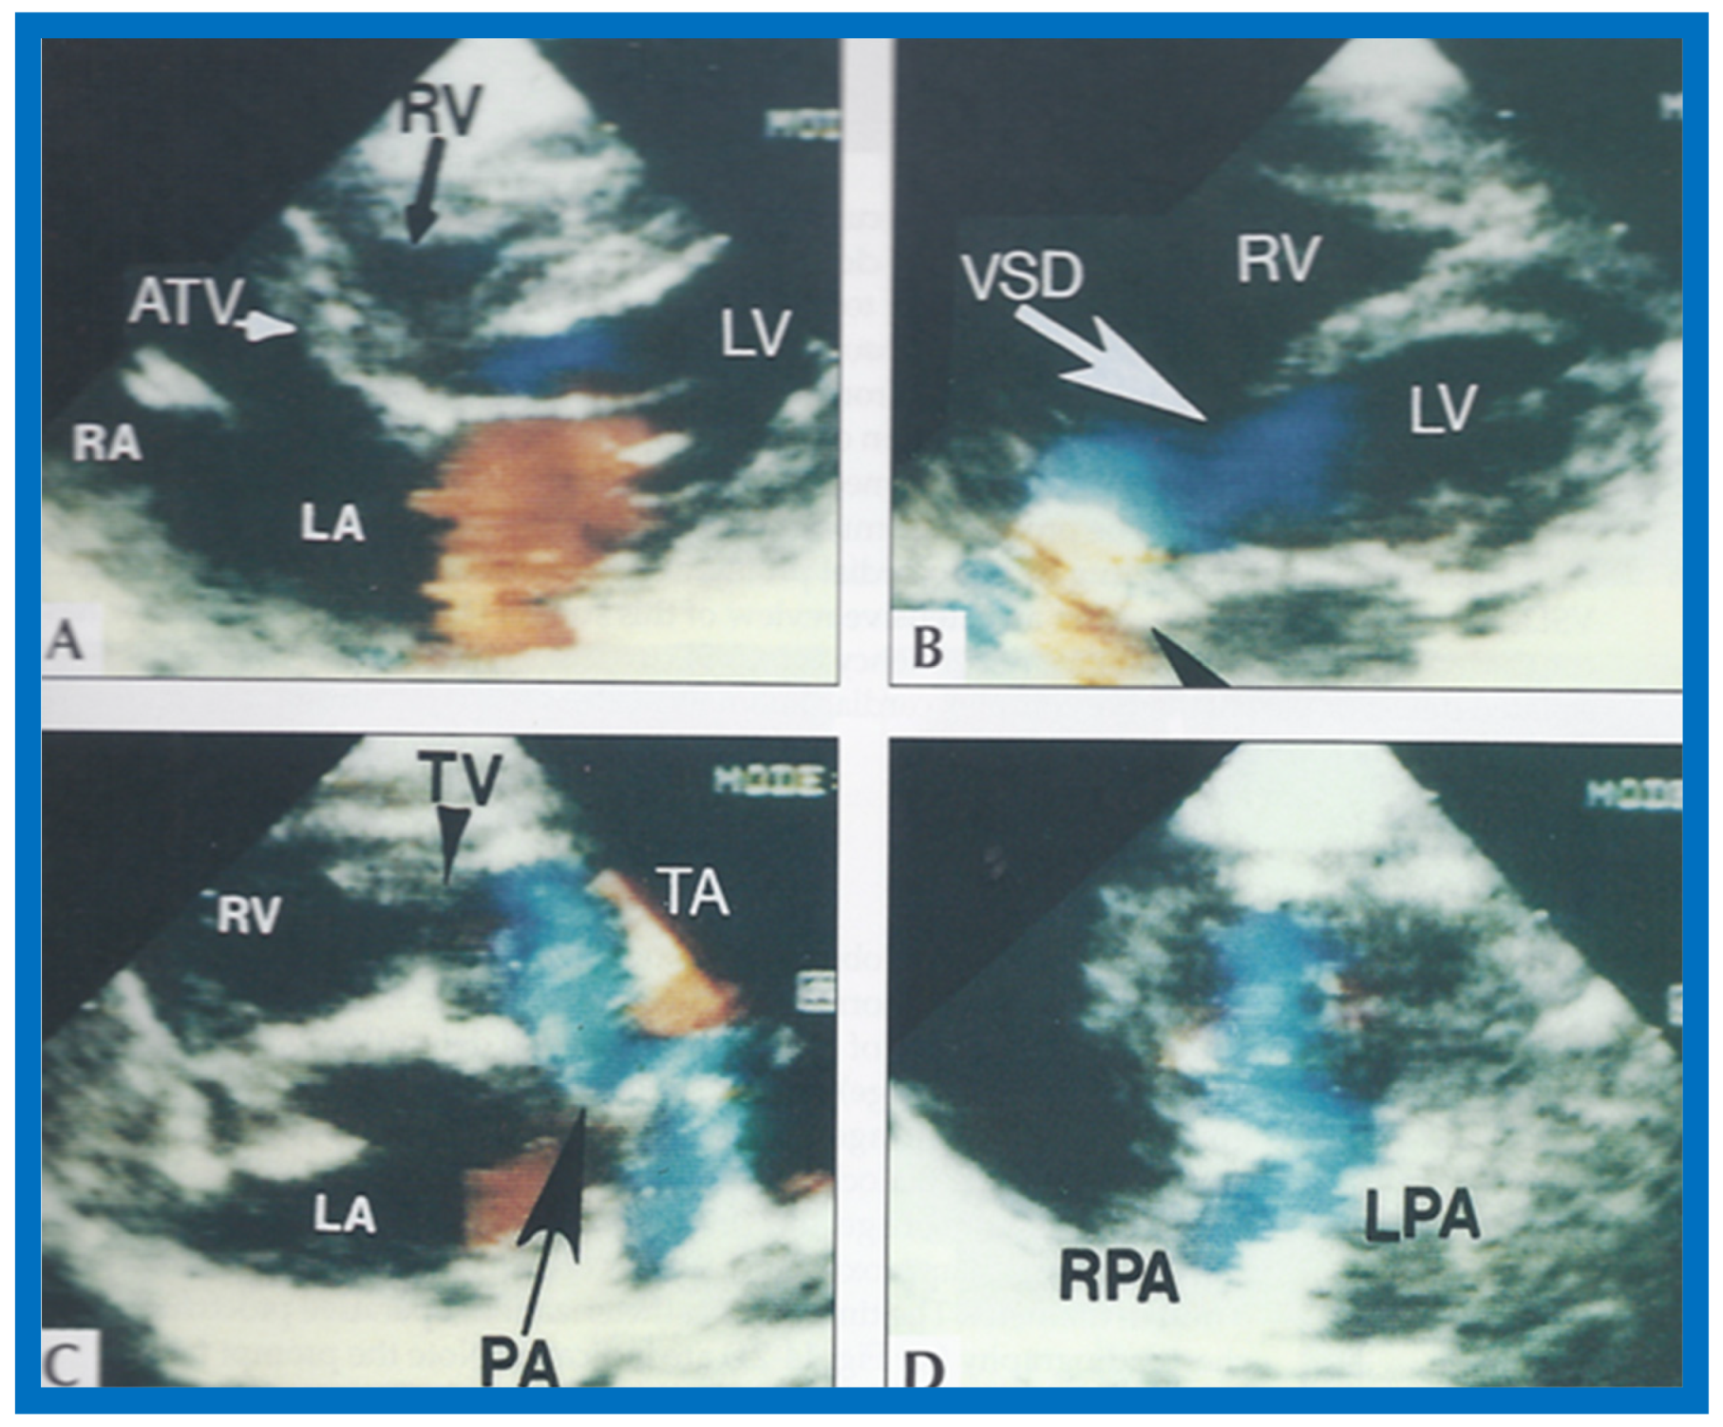

Figure 23.

Two-dimensional echocardiographic video frames demonstrating (a) atretic tricuspid valve (ATV) between the right atrium (RA) and right ventricle (RV), (b) a large subtruncal ventricular septal defect (VSD), (c) thickened and somewhat domed truncal valve (TV) leaflets, and (d) origin of the pulmonary artery (PA) from the posterior aspect of the truncus arteriosus (TA). LA, Left atrium; LV, left ventricle. Reproduced from Rao P.S., et al. [22].

Figure 24.

Video frame from a two-dimensional echocardiographic and color Doppler study demonstrating (A) atretic tricuspid valve (ATV) between the right atrium (RA) and right ventricle (RV) and blood flow from the left atrium (LA) into the left ventricle (LV) across the mitral valve. The RV (arrow) is very small and hypoplastic. (B) LV and RV with a large ventricular septal defect (VSD) below the truncus arteriosus (TA). Turbulent flow across the truncal valve suggests truncal valve stenosis. (C) origin of the pulmonary artery (PA) from the TA by color flow (arrow), and (D) division of right (RPA) and left (LPA) pulmonary arteries from the PA (labeled in d) in a short-axis view. TV, truncal valve leaflets. Reproduced from Rao P.S., et al. [22].

The relationship of the great arteries is examined next in order to classify them into various types [41]. The relationship of the great arteries is established by following the vessels arising from the ventricles until pulmonary bifurcation or aortic arch. In Type I patients with normally related great arteries, the aorta arises from the LV (Figure 20), while in Type II patients with transposition of the great arteries, the PA arises from the LV (Figure 21 and Figure 22). In Type III patients, it may be little more difficult to assign the great artery relationship, and sometimes angiography is needed. In type IV with truncus arteriosus, the limited data [22] suggest that this can be done by echocardiography (Figure 23 and Figure 24).

Then, the ventricular septum is evaluated; the ventricular septum is intact in most Type Ia cases. In children with Type I (normally related great arteries), the VSD supplies pulmonary blood flow (Figure 20) while in patients with Type II (transposition the great arteries), the VSD allows blood to flow into the systemic circuit (Figure 21 and Figure 22). In Type I patients, the VSD is demonstrated by 2D (Figure 20A) and the left to-right shunt across it by color (Figure 20B), pulsed and CW (Figure 20C) Doppler signals. Interrogation of the right ventricular outflow tract and pulmonary artery region is performed; peak Doppler flow velocity across the right ventricular outflow tract and pulmonary valve is helpful in identifying obstruction across these sites. The Doppler data from the VSD and RVOT are also helpful in estimating of pulmonary artery pressures. In these Type I babies, the 2D size of the VSD and the peak Doppler flow velocity across it are useful in quantifying the size of the VSD (Figure 20); the higher the VSD Doppler velocity, the smaller the defect. However, in patients with pulmonary hypertension, severe infundibular or valvar pulmonary stenosis, the VSD Doppler velocities do not reflect the size of the VSD. Barring these exceptions, right ventricular and pulmonary arterial pressure may be estimated using modified Bernoulli equation (RV/PA systolic pressure = systolic BP − 4V2).